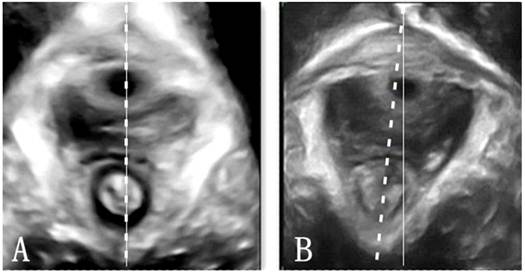

The plane of minimum hiatal dimensions in the midsagittal view was identified by a line between the hyperechogenic posterior aspect of the symphysis pubis and the hyperechogenic anterior border of the puborectalis just posterior to the anorectal muscularis (represented by the single oblique line in Fig. 1) [12]. This line was then used to identify the plane of measurement in the axial plane. Figure 2 demonstrated the morphological findings on the minimal plane of the levator hiatus: levator hiatus area (HA), anteroposterior diameter of levator hiatus (AP) and left to right diameter of levator hiatus (LR). The levator hiatus, puborectalis and pelvic organs were observed in the 3D ultrasound. Two axile lines were defined to get a more accurate hiatal position. The symmetry axis of the bilateral pubic ramus was defined as the pelvic floor axis. The line linking the midpoint of the inner edge of the symphysis pubis and puborectalis was defined as the levator hiatus axis. If there is an intersection angle between the pelvic floor axis and the levator hiatus axis, it is defined that the levator hiatus axis departed from the pelvic floor axis. Using a tomographic ultrasound imaging (TUI), a set of 8 parallel tomographic slices was obtained in the axial plane at intervals of 2.5 mm from 5.0 mm caudal to 12.5 mm cephalad of the plane minimum dimensions. The puborectalis avulsion was identified at the plane of minimal hiatal dimensions and two slices above it on the maximum pelvic floor contraction [21]. The puborectalis avulsion was diagnosed when there was loss of continuity between muscle and pelvic sidewall at least on one slice. Avulsion includes full avulsion and partial avulsion. Full avulsionwas determined if the loss of continuity between muscle and pelvic sidewall is seen on all the 3 slices. Partial avulsion is diagnosed when loss of continuity between muscle and pelvic sidewall is seen on at least one slice. In normal condition, the urethra, vagina and rectum arranged tightly in a line in ventridorsal orientation inside the levator hiatus. If the other structures such as uterus, bladder, vagina vault, or intestinal canal other than the urethra, vagina and rectum were found in the hiatus, we defined the organs arranged abnormally.

Figure 1

The plane of minimal hiatal dimensions in the mid-sagittal plane (A) and axial plane (B).

Figure 3

Position of the pelvic hiatus. A, the axis of levator hiatus and pelvic floor overlapped in nullipara patients; B, levator hiatus axis departed from the pelvic floor axis in POP woman. Dot line, levator hiatus axis; Solid line, pelvic floor axis.